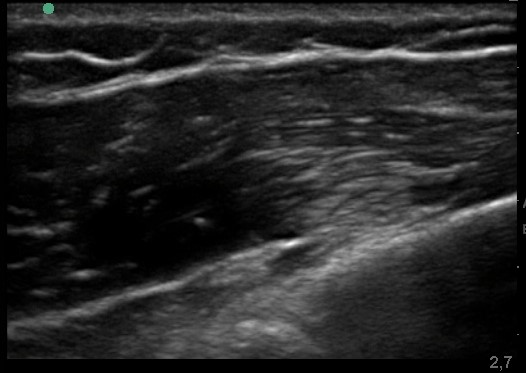

Lesione muscolare evidenziata all’ecografia

Trattamento infiltrativo mirato sotto guida ecografica

L’utilizzo dell’ecografia permette di:

individuare con precisione la sede del problema

guidare eventuali trattamenti in modo mirato

Nel caso descritto, è stato eseguito un trattamento infiltrativo locale con:

10 cc di soluzione glucosata al 5%

somministrata nella zona dolente

sotto guida ecografica

L’obiettivo non è “coprire il dolore”, ma intervenire direttamente sull’area responsabile dei sintomi.

Dopo la seduta, il paziente ha riferito una rapida riduzione della dolorabilità locale.